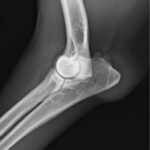

- A los 4-6 meses, si no hay ningún síntoma, es suficiente realizar una única radiografía mediolateral en posición neutra, o sea en 90-100º de flexión.

- Si hay síntomas (cojera), o si en la ML hay alteraciones (o si no estamos seguros) realizaremos siempre otra proyección mediolateral en flexión (45º) y una anteroposterior (lo ideal: ligeramente oblicua con 15 grados de pronación, o sea rotación interna)

- A los 12 meses de edad, para el informe definitivo, necesitaremos SIEMPRE una pr. mediolateral en extensión no forzada 110-140º, y una anteroposterior estándar.